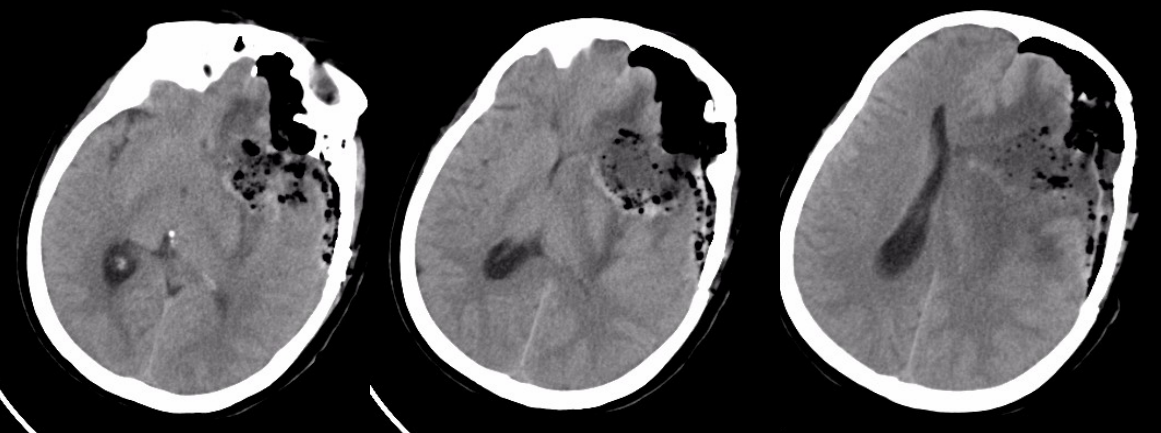

术后半年MRI增强